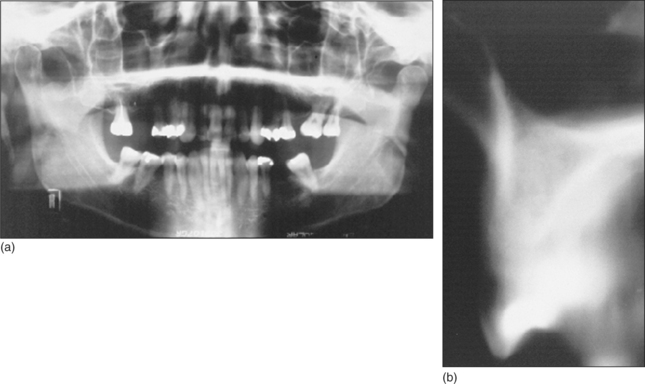

Special investigations

The height, width and overall shape of the residual ridge are evaluated from study models and radiographs to ensure adequate bone to support the implant. Articulated study casts are required to evaluate the occlusion; there should be no excessive forces on the implant during lateral or protrusive excursions of the jaws. A preliminary assessment of the ideal position and angulation of implants may be made from the study casts, in conjunction with a surgical stent (Fig. 11.19). Radiographs (Fig. 11.20) will determine the quality of the bone and help in assessing suitable sites for implants. The radiographs should adequately demonstrate important structures (the inferior alveolar neurovascular bundle, the floor of the nose, the maxillary antrum and adjacent teeth).

image

Fig. 11.20 (a) A panoramic radiograph yields much information about the teeth and jaws, but is unhelpful in determining the suitability of the bone at the proposed site of an implant in tooth 16 position. (b) A tomographic view of the bone in the tooth 16 area gives more information about the quality of the bone and the height of the maxillary sinus.

Most X-ray units do not give 1:1 magnification of the image: this must be borne in mind when planning the optimum dimensions of an implant from the radiographs. An acrylic stent may be used to determine the planned location of an implant. The stent is fitted over the teeth or edentulous jaw (Fig. 11.19) when the radiograph is taken.

CT scans (Fig. 11.22) are gaining popularity in the assessment of a patient before implant surgery. Cone-beam CT scan units offer improved functionality and convenience over conventional CT scanning units (http://www.imagingsciences.com/pro_iCAT_features.htm). In the above illustration, a patient requesting implants in the right posterior maxillary sextant has undergone an I-Cat scan to assess the bone. There is a deficiency in the buccal bone in sections 34–36, and clearly bone grafting is required before implants can be placed.